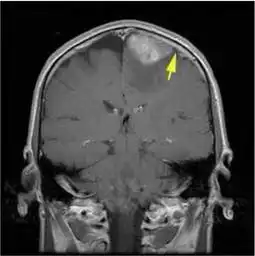

一看就有大病的头像脑瘤 描述: 一看就有大病的头像脑瘤 创立日期: 2025-05-22 00:07:12 图片数量: 0 pics 浏览量: 通过脑室内注射cart首次消灭致命脑瘤的研究团队,这次盯上了乳腺癌脑转移 最新科技自动掏耳神器,360无死角,让你爽翻天 右乙状窦区脑膜瘤纤维型mri病例图片影像诊断影像园 犬脑膜瘤的综述 6岁儿童一口气读不了白日依山尽不是贵人语迟是脑肿瘤 中华医学网 腹腔大病灶,快来围观有病理影像医学和核医学讨论版 嗅沟脑膜瘤olfactorymeningiomamrict病例图片影像诊断分析 美科学家研发读心程序可将大脑想法转换成语音 口苦可能是大病预警,一定要重视 农夫捡到一大堆子弹吓得够呛,清洗后发现透亮鉴定后大喜 类别: 2025头像大全